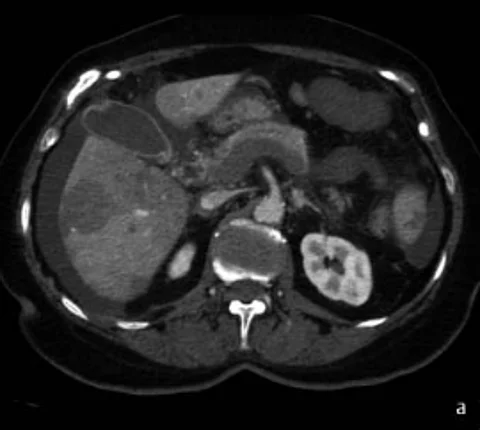

Quiz70-Jährige mit akutem Abdomen

Die 70-Jährige stellte sich mit dem klinischen Bild eines akuten Abdomens in der Notaufnahme vor. Sie gab progrediente Bauchschmerzen seit 5 Tagen an. Bei der klinischen Untersuchung ergaben sich abdominal eine diffuse Abwehrspannung und fehlende Darmgeräusche. Das Basislabor erbrachte keinen wegweisenden Befund. Es erfolgte eine…

QuizAuflösung: 70-Jährige mit akutem Abdomen

Befunde (s. Bildergalerie)

1. Thrombose der V. portae, V. lienalis und V. mesenterica superior

2. Akute Ischämie des Dünndarms

3. Perfusionsdefekte der Leber und Milz

4. Aszites